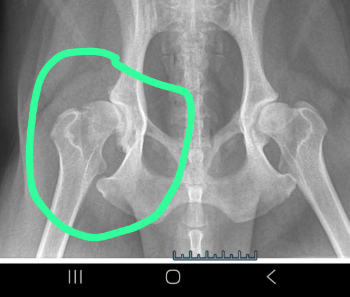

Baily braucht bitte dringend Eure Hilfe ❤️ Er braucht ganz dringend eine neue Hüfte .

Den er ist erst 6 geworden u.benötigt eine neue Hüfte .Bis dahin bekommt er Spritzen gegen die Schmerzen und Entzündungen.Er ist ein ganz großer Rückhalt für meinen Bruder der an Asbergersyndrom (leichte Form)leidet.